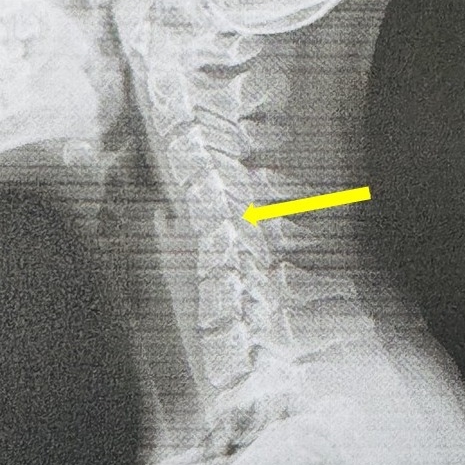

An X-ray revealed a shocking truth – her cervical spine had lost its natural inward curve and, in some areas, vertebrae showed signs of slippage.

Her condition, commonly known as “text neck”, is an early warning of premature cervical degeneration.